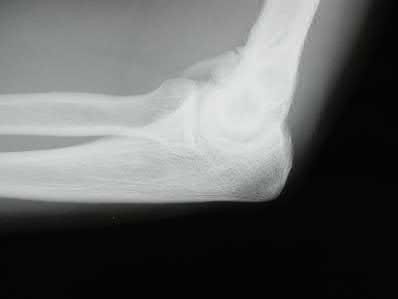

Figures A and B show a distal humerus fracture without traction (A) and with traction (B) applied. Illustration A shows the same fracture after bicolumnar plating. Illustration B shows the different surgical approaches to the distal humerus (A, Campbell triceps splitting; B, O'Driscoll triceps reflecting anconeus pedicle [TRAP]; C, Bryan-Morrey triceps reflecting; D, olecranon osteotomy)